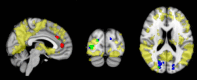

Recent imaging studies have demonstrated functional brain network changes in patients with Alzheimer's disease (AD). Eigenvector centrality (EC) is a graph analytical measure that identifies prominent regions in the brain network hierarchy and detects localized differences between patient populations. This study used voxel-wise EC mapping (ECM) to analyze individual whole-brain resting-state functional magnetic resonance imaging (MRI) scans in 39 AD patients (age 67 ± 8) and 43 healthy controls (age 69 ± 7). Between-group differences were assessed by a permutation-based method. Associations of EC with biomarkers for AD pathology in cerebrospinal fluid (CSF) and Mini Mental State Examination (MMSE) scores were assessed using Spearman correlation analysis. Decreased EC was found bilaterally in the occipital cortex in AD patients compared to controls. Regions of increased EC were identified in the anterior cingulate and paracingulate gyrus. Across groups, frontal and occipital EC changes were associated with pathological concentrations of CSF biomarkers and with cognition. In controls, decreased EC values in the occipital regions were related to lower MMSE scores. Our main finding is that ECM, a hypothesis-free and computationally efficient analysis method of functional MRI (fMRI) data, identifies changes in brain network organization in AD patients that are related to cognition and underlying AD pathology. The relation between AD-like EC changes and cognitive performance suggests that resting-state fMRI measured EC is a potential marker of disease severity for AD.